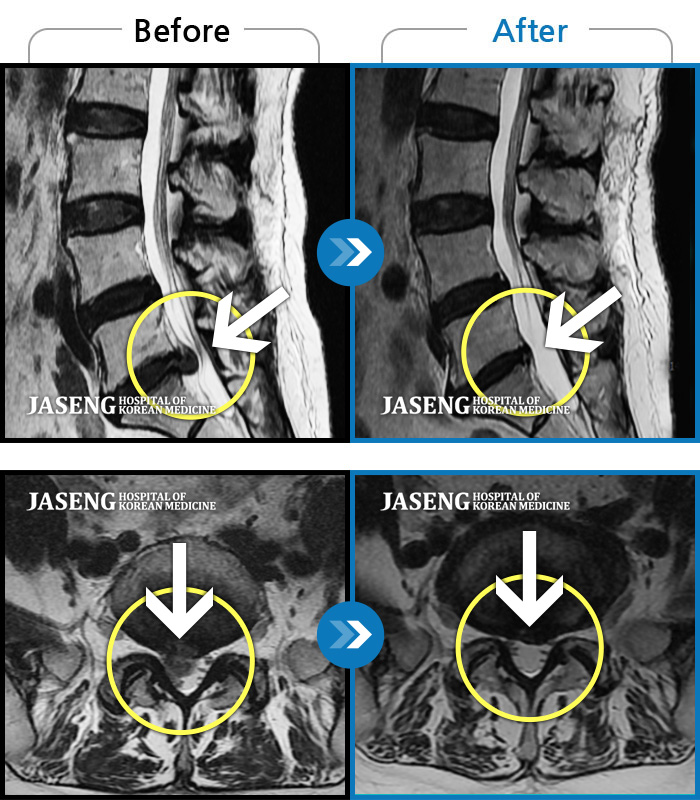

허리디스크

목동 · 고웅 원장

허리통증으로 보행 불가. 우측 다리의 통증과 저림, 화끈거리는 통증과 차가운 느낌 번갈아 나타남

촬영시기

2020.12.18 ~ 2024.11.15